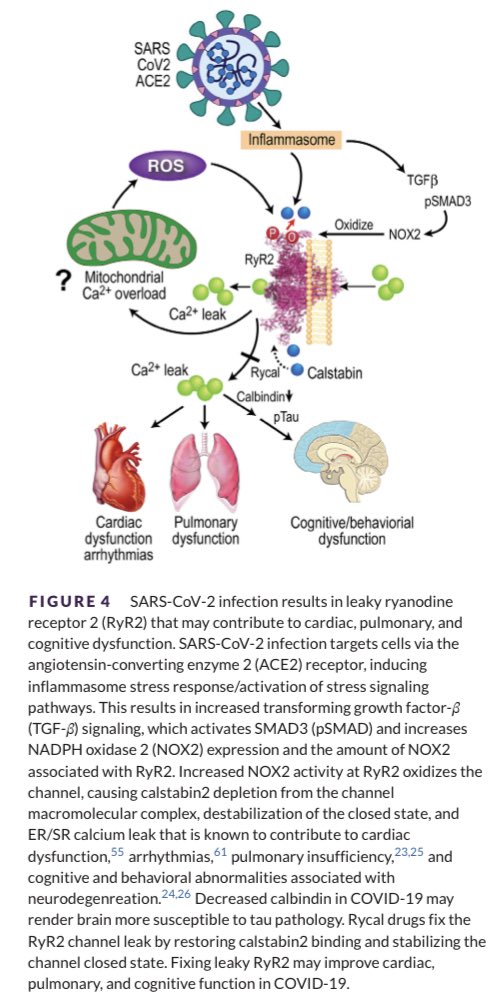

Die Studie … verbindet die Entzündungsreaktion, die bei einer SARS-CoV-2-Infektion auftritt, mit Wegen, die eine Tau-Hyperphosphorylierung verursachen, die typischerweise mit #Alzheimer in Verbindung gebracht wird. Die Daten deuten auch auf eine Rolle für den undichten Ryanodin-Rezeptor 2 (RyR2) in der Pathophysiologie der SARS-CoV-2-Infektion hin.

Anhaltender Hirnnebel und kardiale Symptome bei Menschen mit COVID-19 veranlassten Marks und seine Mitautoren zu untersuchen, wie die Ryanodin-Rezeptoren bei COVID-19 beeinflusst werden. “Was wir gefunden haben, ist, glaube ich, ziemlich unerwartet”, sagte Marks.